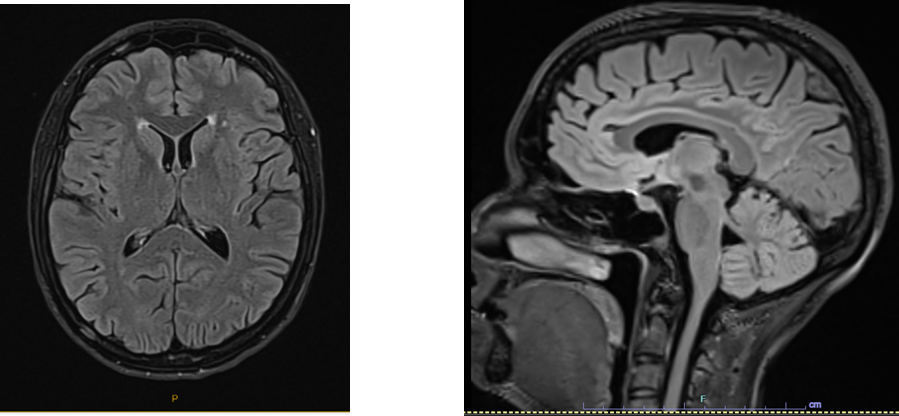

MRI brain: mild chronic ischaemic changes.

Repeat. CT brain and MRI brain MRA normal. Mild chronic ischaemic change.

MRI – no T2 callosal lesions – chronic ischemic change